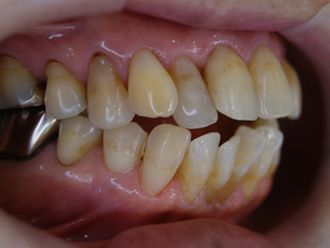

右上4番5番欠損の症例ですが、3番犬歯を削る量をできるだけ少なくしてブリッジにしています。(6番はもともと冠が入っていました。普通はこのようにぐるっと削るわけです。)

当院では、できるだけこのように自分の歯を削らないでいいようなブリッジをお勧めしています。

右上ブリッジ1.jpg

右上ブリッジ2.jpg

右上ブリッジ3側面観.jpg